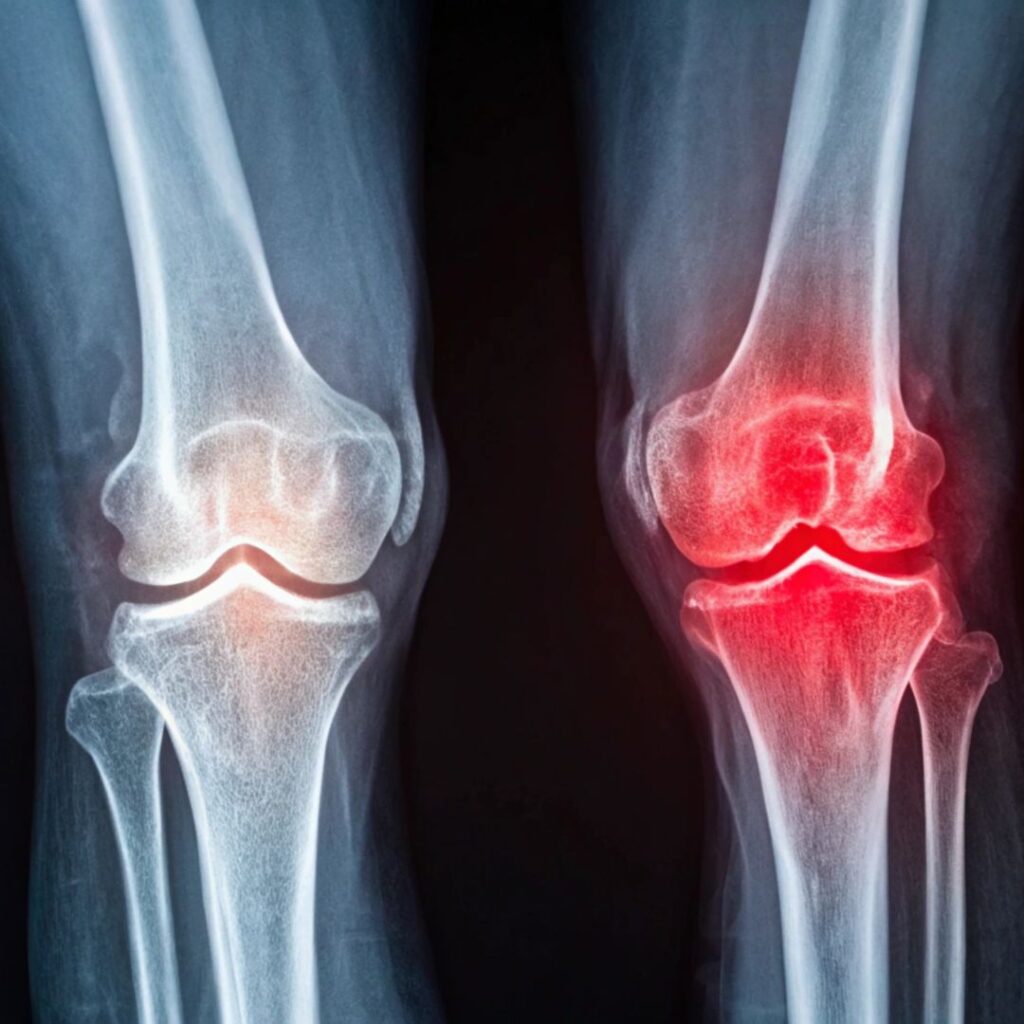

Severe knee pain or stiffness can make daily activities—like walking or climbing stairs—difficult. Knee Joint Replacement replaces the damaged joint with durable implants to restore smooth, pain-free movement. Performed by Dr. Lokesh Dabral, a leading Orthopedic and Joint Replacement Surgeon in Dehradun, the surgery ensures precision, faster recovery, and lasting relief. It is ideal for patients with osteoarthritis, rheumatoid arthritis, or post-traumatic damage. Post-surgery rehabilitation helps rebuild strength, improve flexibility, and restore an active, confident lifestyle.